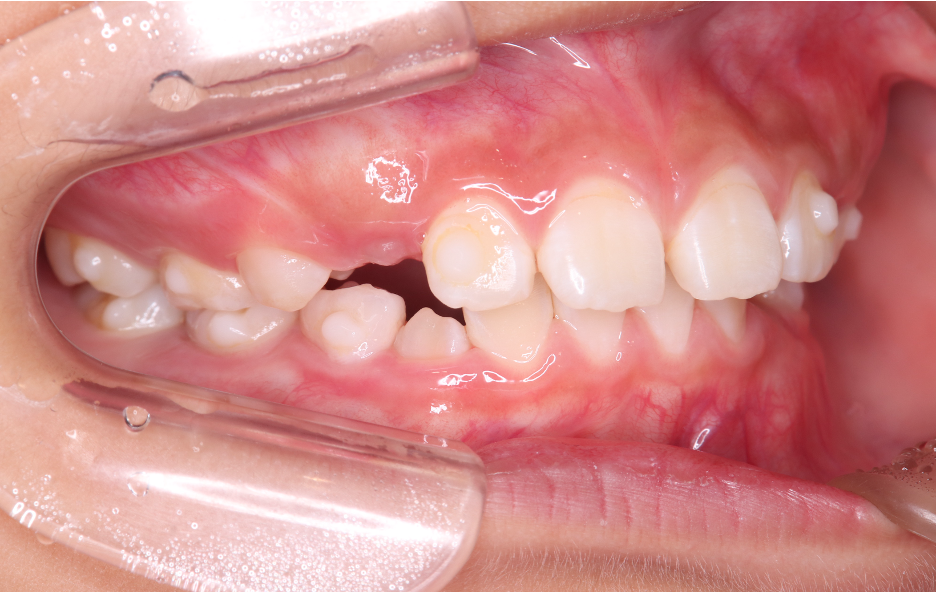

Before